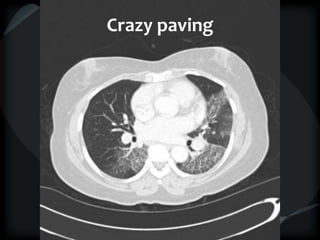

Airspace Patterns

 Inter and intralobular septal thickening / ground glass/crazy paving

Crazy paving